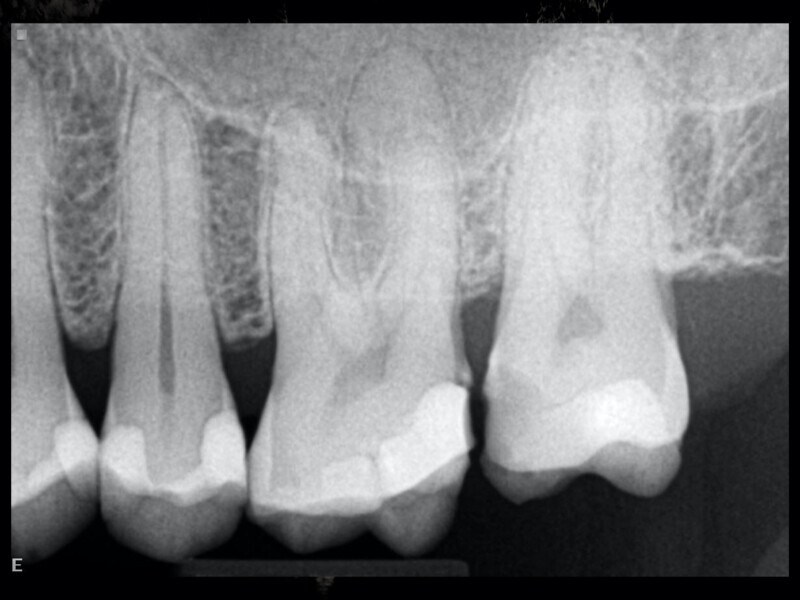

Clinical management of maxillary second molar root canal therapy in different anatomical situations